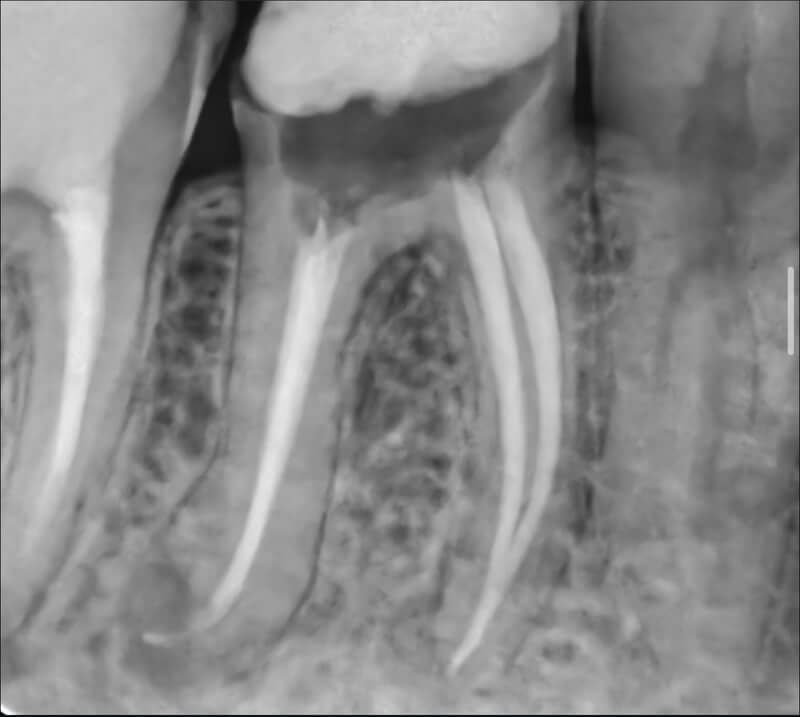

Endodonția este o ramură esențială a stomatologiei, axată pe diagnosticarea, prevenirea și tratamentul afecțiunilor pulpei dentare și a țesuturilor periapicale. Această specialitate joacă un rol crucial în salvarea dinților naturali, evitând extracțiile și menținând sănătatea orală pe termen lung. Prin tehnici avansate și echipamente de ultimă generație, endodonția asigură tratamente precise și eficiente, contribuind la redarea sănătății și funcționalității dinților într-un mod durabil și predictibil.

Utilizarea tehnicilor moderne asigură un tratament rapid, precis și confortabil pentru pacient.